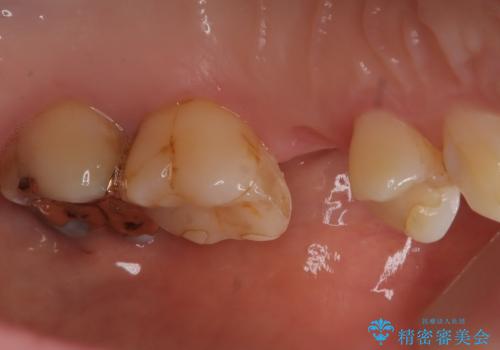

- 根管治療をしている歯が破折し、抜歯となってしまいました。

抜歯した部位に対して、はじめに可撤性部分義歯,ブリッジ、インプラントによる治療方法とそれぞれの利点と欠点について説明を行った結果、インプラント治療を希望されました。さらに、インプラント治療の術前・術後口腔内管理の重要性、手術内容,費用などを説明し、十分なインフォームド・コンセントを得たうえで治療を開始しました。